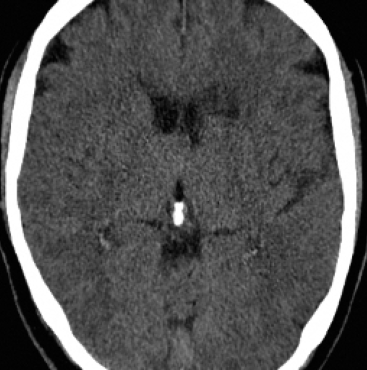

The former is a randomised-controlled trial that collected brain imaging data, primarily CT scans, from 3035 patients exhibiting stroke symptoms. The scans were conducted at two time points: immediately after the patients’ hospital admission and again between 24-48 hours later. Radiologists involved in the trial assessed the presence or absence of early ischemic signs and recorded the location of any identified lesions for positive scans. In our analysis, we considered a total of 5681 scans, of which were classified as negative (no lesion), while the remaining scans were positive. In particular, We considered 11 slices for each scan and resized each slice to . For more detailed information about the trial protocol, data collection, and the data use agreement, please refer to the following URL: IST-3 information.

4.3 Counterfactual Examples

In Figures 2 and 4 we display examples of healthy images and anomaly maps obtained with the different approaches. We can observe that f-Ano GAN is not able to generate credible counterfactuals and generally produces images of poor quality and unrealistic appearance. On the other hand, the approaches based on diffusion models are able to create more high-quality results. However, the ones obtained with CG and CFG seem to present some artifacts, which may not only impact the realism of the counterfactual examples but also the precision of the anomaly maps obtained from them. In order to better quantify the capability of these methods to accurately segment pathological areas, we compute the Dice scores of the anomaly maps they generate.